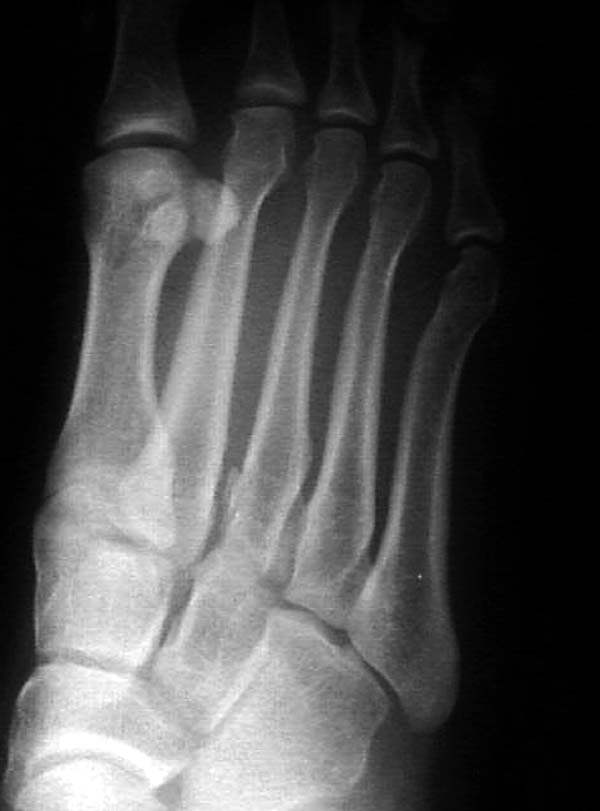

Ренген снимки прислал один из моих коллег из бывшего союза, просит совета.

К нему в клинику обратился с жалобами 24 летний

студент, получил травму две недели назад катаясь на скейтинг борд.

Ходить прихрамываяь. Небольшая отечность на тыле стопы, неврологических и сосудистых изменений нет.

Подскажите, что предпринимать больному? Снимки представлены.

Имя     : AP 3.jpg